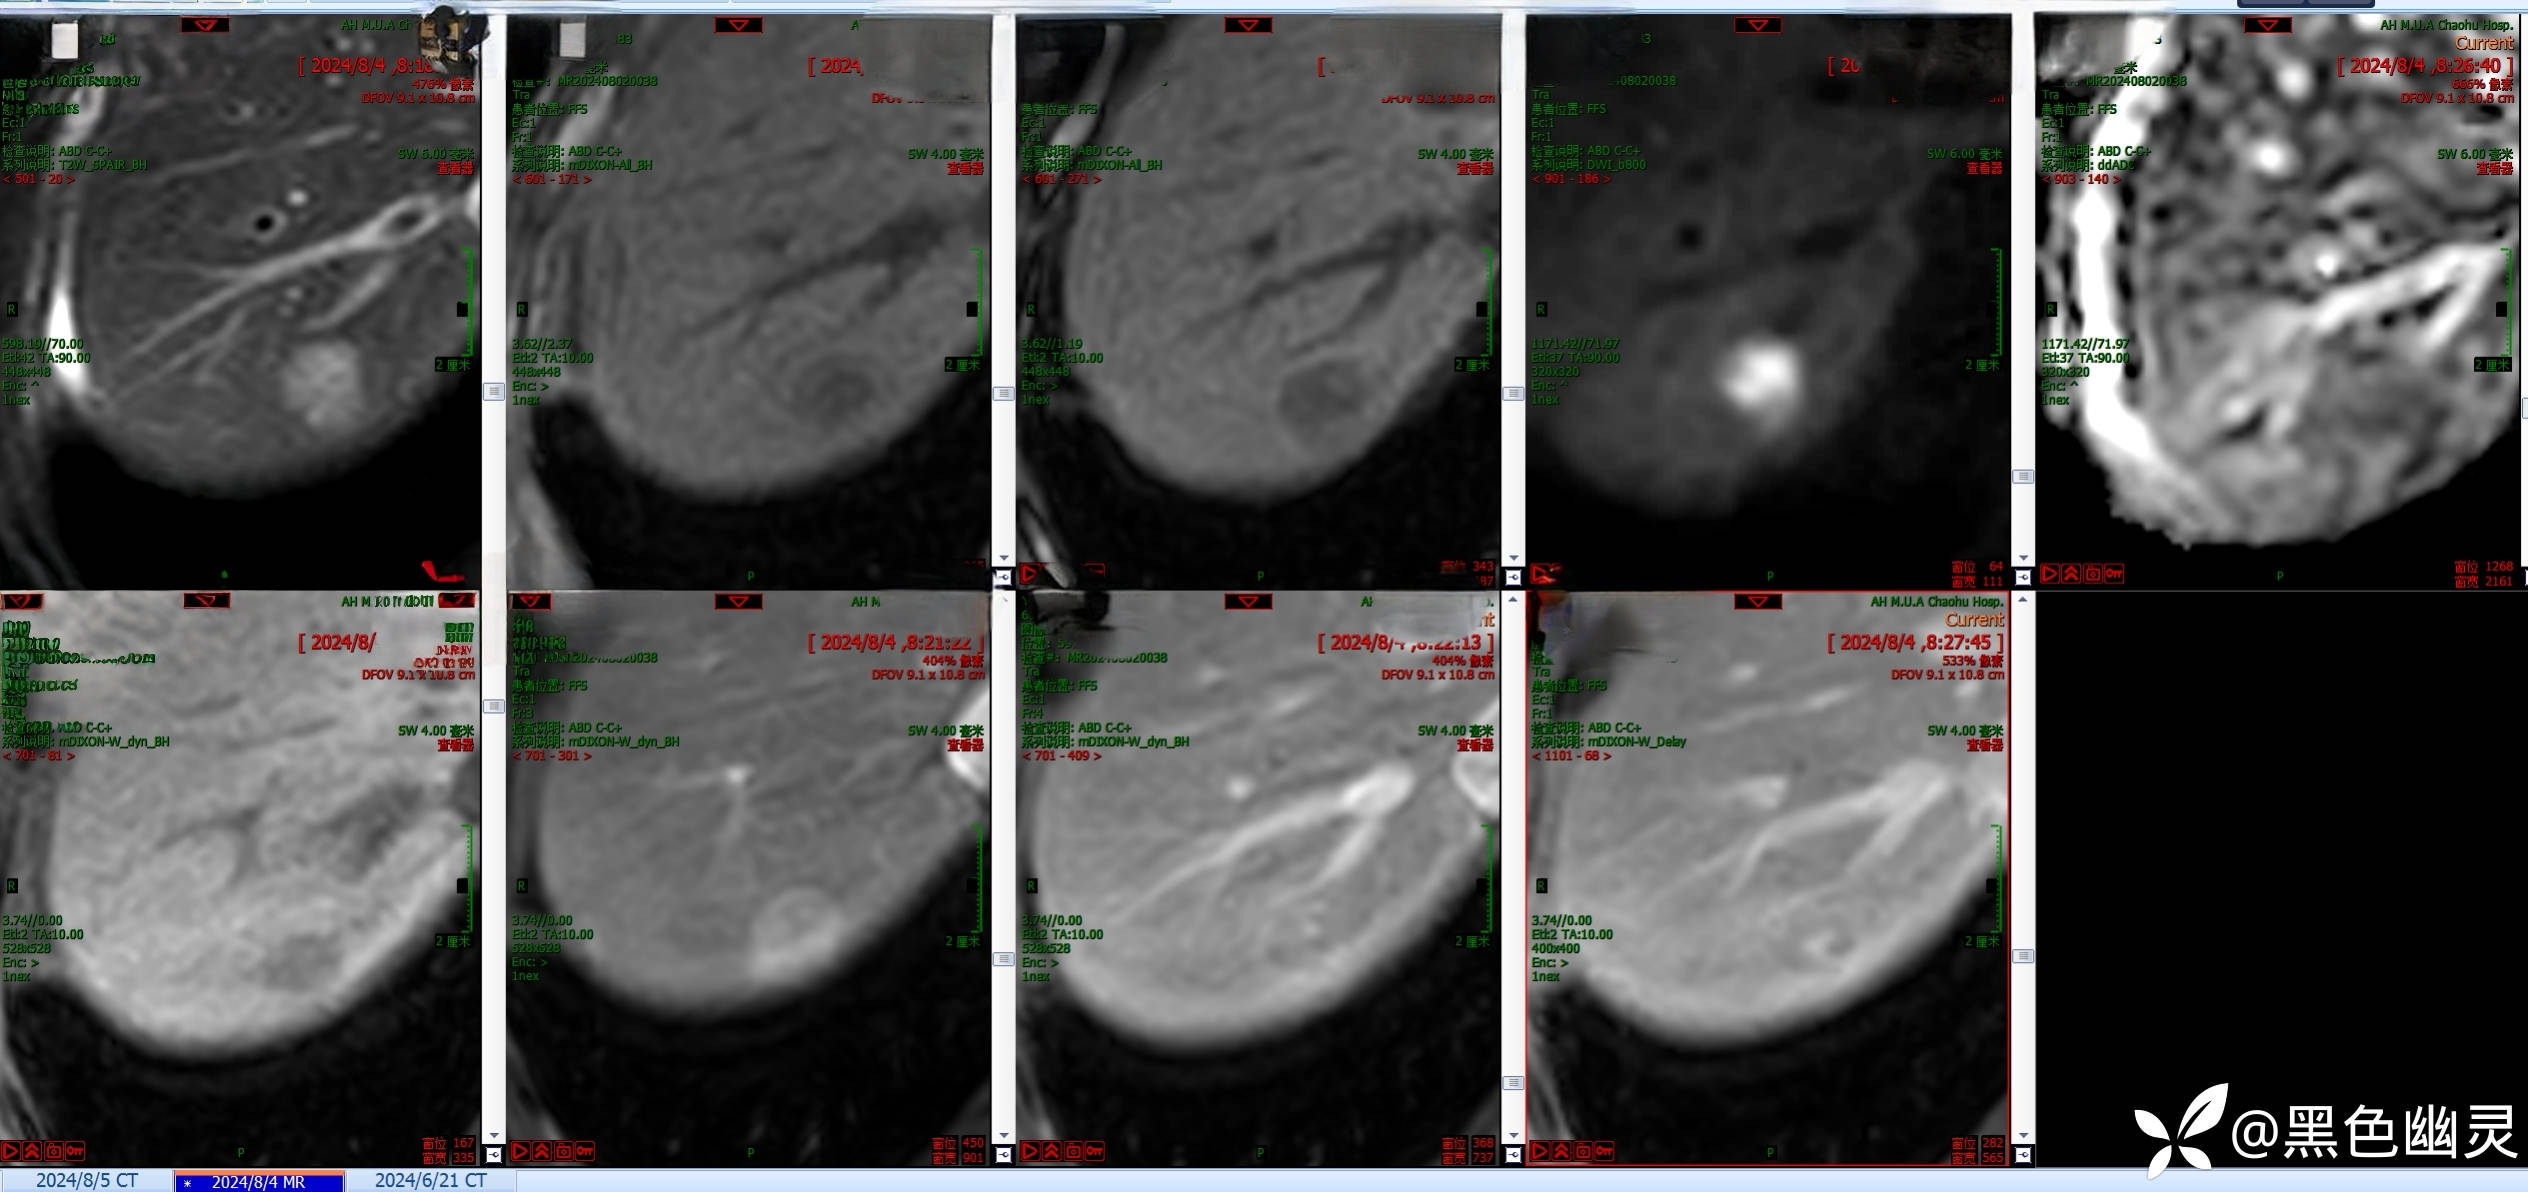

患者,男,68岁。1月前患者体检时发现肝脏右后叶结节,无腹痛、腹泻,无呕吐,无鼻塞、流涕,尿量正常,门诊拟肝右叶占位,收住我科。病程中患者一般情況尚可,无量减少,睡眠欠佳,大便基本正常,体重未见减轻。

查体,神清,全身皮肤巩膜无黄染,腹部压痛阴性,反跳痛阴性,双下肢无浮肿。